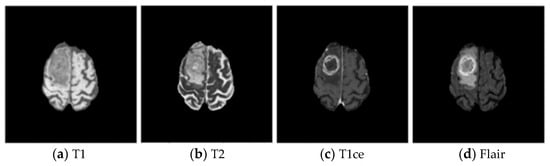

Brain tumors are new organisms, which grow in the cranial cavity and can be divided into primary and secondary tumors. According to cancer statistics in recent years, the incidence of brain tumors accounts for about 1.5% of whole-body tumors, but the death rate is as high as 3% [1]. Glioma is one of the most common malignant tumors in the brain—a tumor, which originates from glial cells. There are two types of gliomas: high-grade gliomas (HGG) and low-grade gliomas (LGG) [2,3]. Magnetic resonance imaging (MRI) is one of the most commonly used tools in clinical medicine to examine the brain due to its non-invasive nature, which protects the body from ionizing radiation, and its superior soft tissue contrast [4]. The MRI scanner was adjusted with different parameters to obtain four modalities—T1, T2, T1ce, and Flair—as shown in Figure 1, which are multimodal brain MRI images of the same patient with the same acquisition device using different parameters. Due to the widespread use of MRI equipment in brain examinations, a large amount of brain MRI image data are generated in the clinic, and it is impossible for physicians to manually annotate and segment all images promptly. The tissue structure in brain tumor images varies from individual to individual, from stage to stage, and from device to device, and manual segmentation of brain tumor tissue relies on the physician’s personal experience. Therefore, the research focuses on how to segment brain tumors efficiently, precisely, and fully automatically [5].

Figure 1. Brain tumor images in different modes.